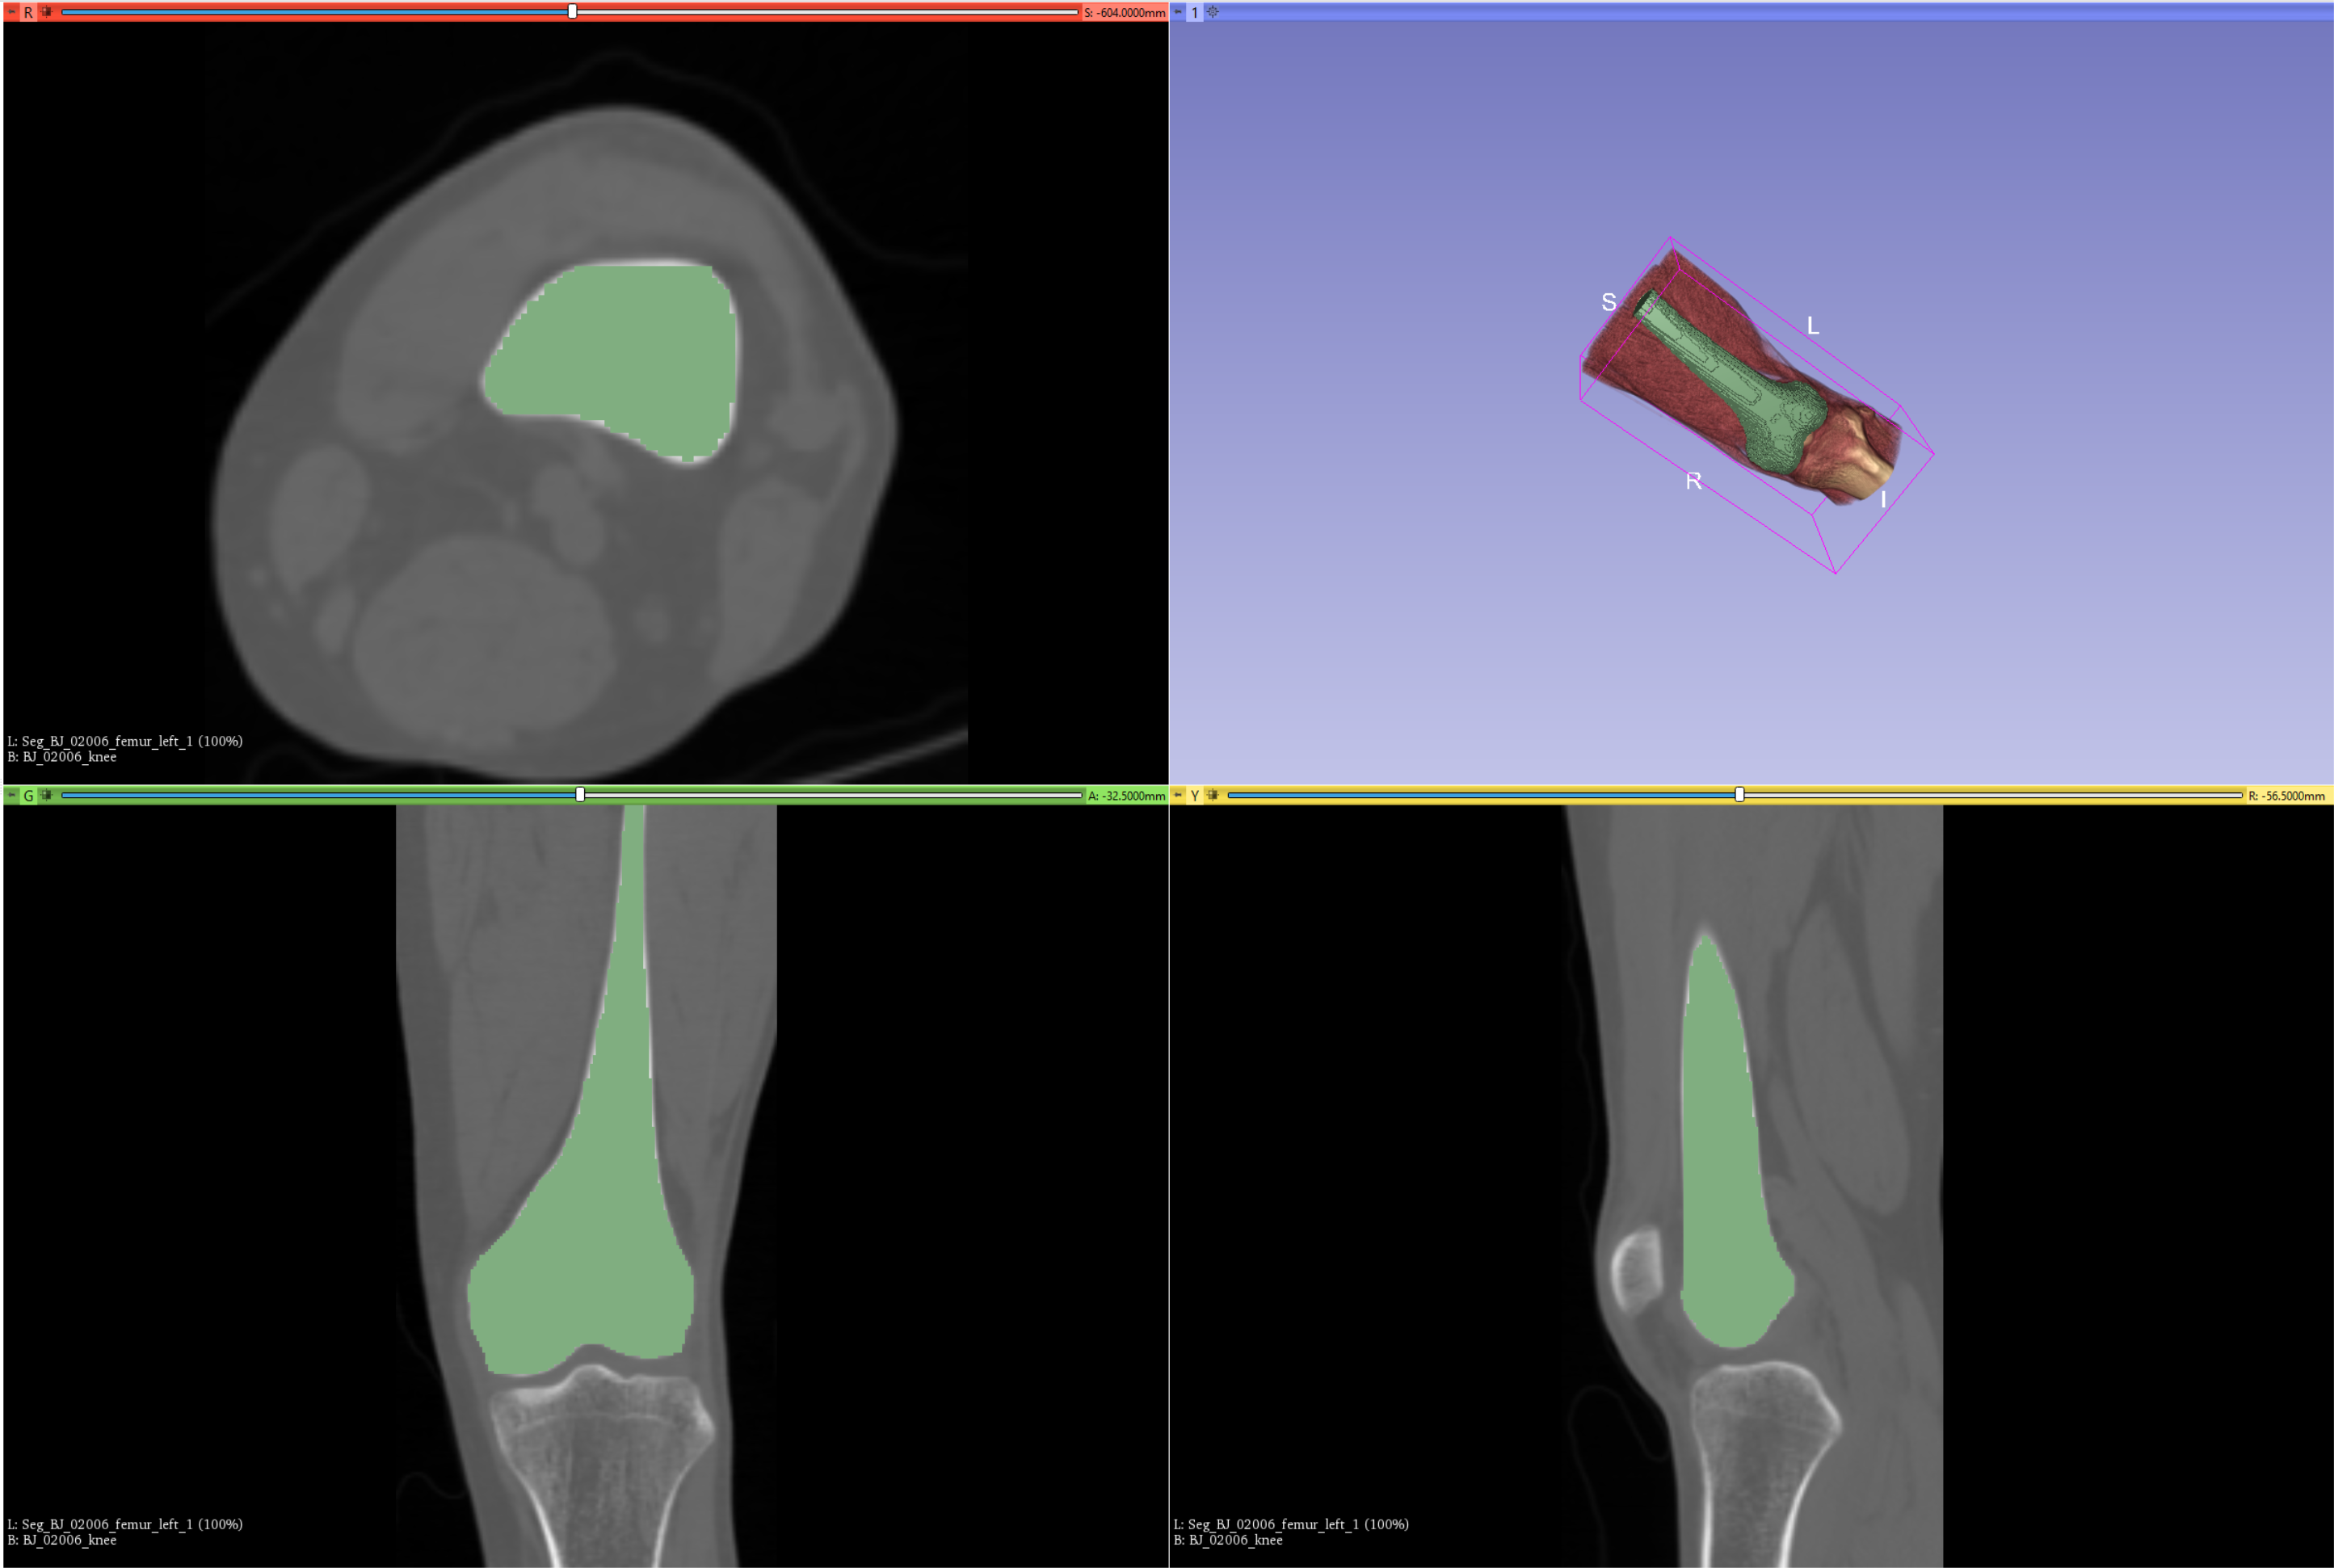

我要实现的目的是:将原始stl切下与原始数据重合的部分,并且用一个与原始数据一样的尺寸存放,并且对应的空间坐标一致(原点、spacing、direction)。

如下输入原始数据:

原始的stl数据,绿色部分:

对齐后的效果如下:

stl对齐后的volume信息如下

对齐后的渲染效果如下